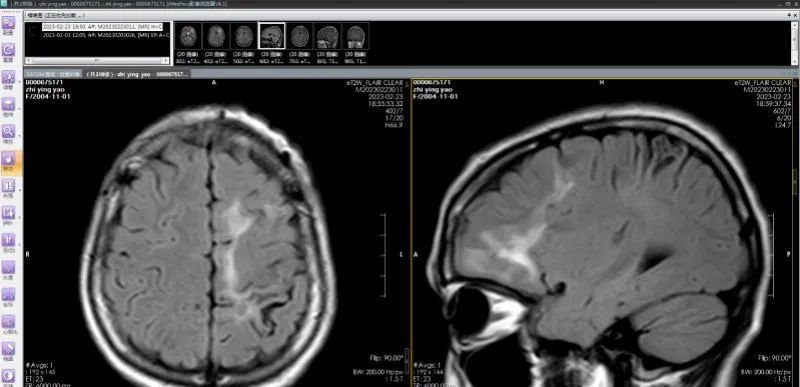

多发脑软化灶实为虫体在颅内爬行产生的损伤,患者癫痫发作的根源在于寄生虫对大脑的炎性刺激,造成大脑异常放电。

脑软化灶实为虫体在颅内的爬行轨迹;(左)从下往上移动,(右)从后往前移动